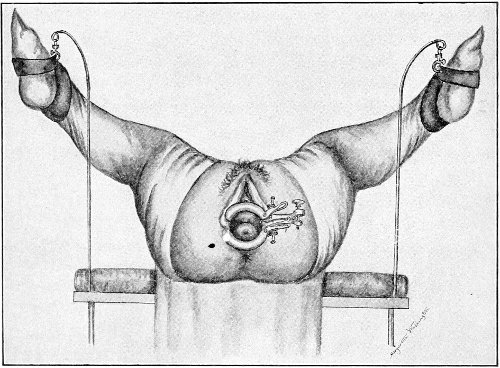

Examination of External Genitals and Pelvic Structures.—To examine the external organs of generation and the pelvic viscera the woman should be placed upon a table. In some cases the physician may be obliged, for want of proper facilities or on account of the physical condition of the patient, to make his examination upon a bed. Such an examination, however, is never so satisfactory or so thorough as the examination made with the woman upon the examining-table. A great number of gynecological tables have been introduced. The one which seems to the writer the best, on account of its simplicity and the perfect relaxation of the abdominal muscles furnished by it, is shown in the accompanying illustration (Fig. 1). It is a plain wooden table, at the foot of which are attached the upright supports for holding the stirrups for the feet, such as have been devised by Dr. Edebohls. By this arrangement the feet and legs are supported without any effort on the part of the woman; when the buttocks are drawn well down to the foot of the table there is a certain amount of flexion 23 of the pelvis upon the trunk, and the most complete attainable relaxation of the abdominal muscles is secured.

Fig. 1.—Woman in the dorsal position with feet supported in Edebohls’ stirrups.

For operation upon the perineum the woman should be placed in the dorso-sacral position (Fig. 1, page 23).